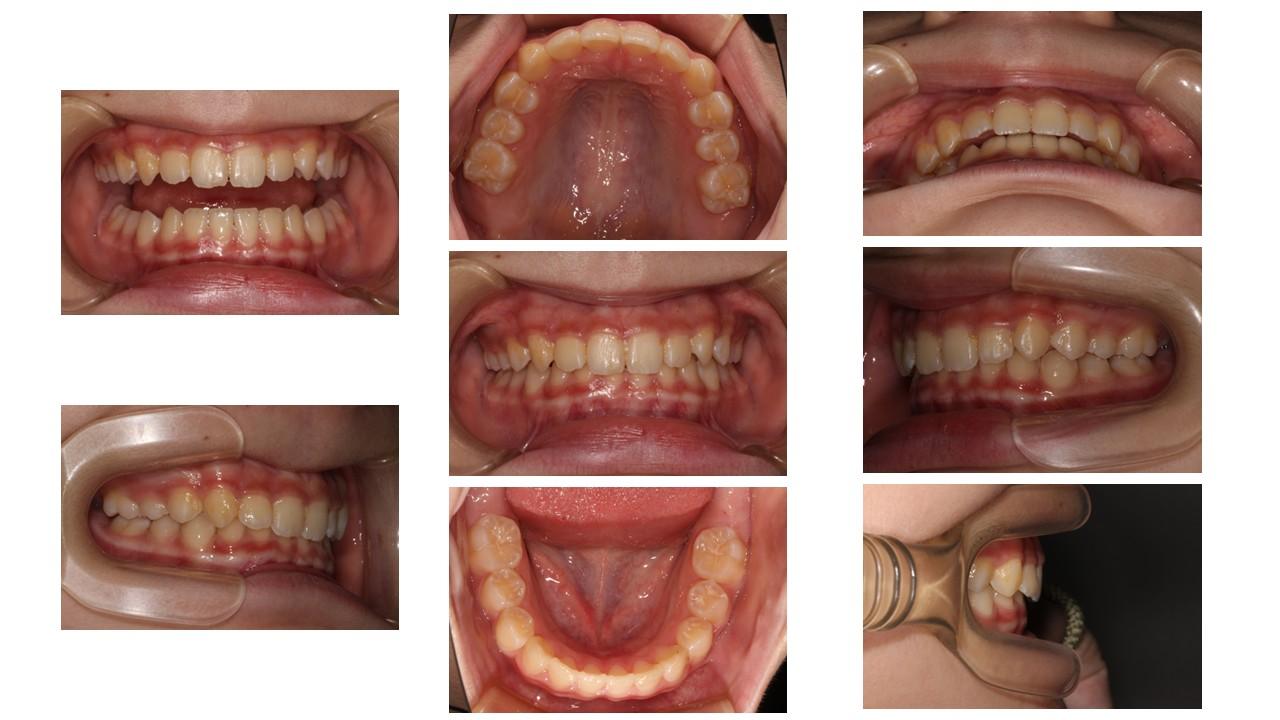

叢生を治療し、歯並びをきれいに整えることは、毎日の歯磨きを容易にし、虫歯や歯周病を予防するとともに、顎関節や全身の健康を守るための大切な投資となります。

将来むし歯や歯周病にならないためには、「お子さまのうちから歯ならびとかみ合わせを整えること」が、とても大切です。歯並びが整うことで歯ブラシがしやすくなり、毎日の歯磨きの効果がぐんと高くなり、むし歯や歯周病を予防することができます。

これが将来のお口のトラブルを防ぐための最短ルートだと考えています。